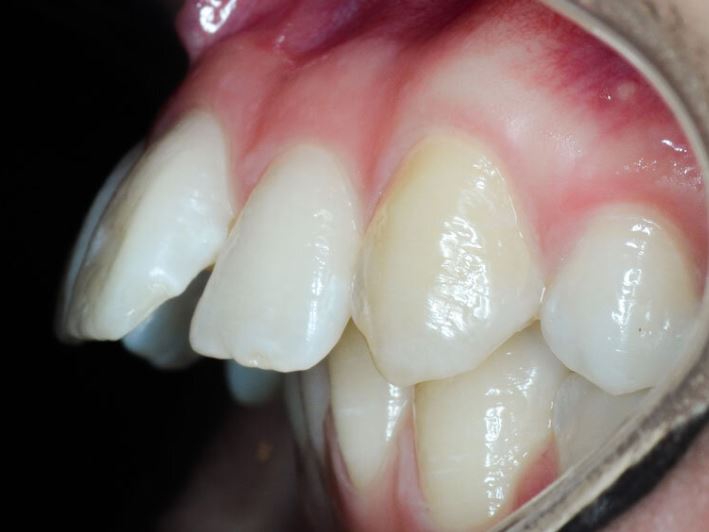

Опустились дёсны в нескольких местах, обнажились шейки зубов. Чувствительные, болят от прикосновений, могут реагировать на холодное, горячее, сладкое.

Ситуация как примерно на пик2.

Предлагали два варианта:

1) Пластика десны, когда кусок кожи с нёба отрезают и пришивают к десне, чтобы закрыть оголившийся участок

2) Простое заделывание чувствительных мест пломбой/аналогом пломбы без пластики дёсен.

В первом случае меня беспокоит, что будет, если на оголившемся участке зуба есть кариес (сейчас из-за общей более тёмной природной пигментации шеек зубов + налёта не понятно), и я зашью этот кариес под кожу? Кариес будет прогрессировать под десной?

А во втором случае, дохтур сказал, что к заделанным пломбой шейкам зубов десна уже назад не прирастёт, даже если пересадить, то есть пластика дёсен будет невозможна.